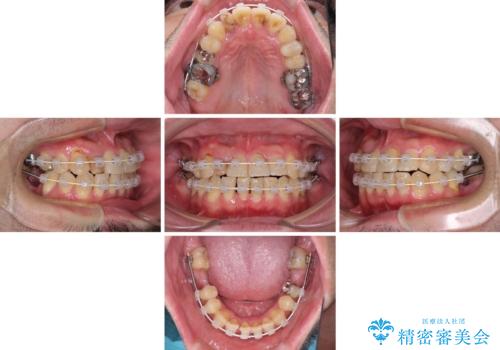

咬み合わせは受け口傾向であり、上顎前歯の叢生が顕著であったことから、第1小臼歯抜歯による矯正治療も検討しましたが、下顎大臼歯を左右ともに抜歯するため、非抜歯による矯正治療を行うこととしました。

矯正治療でインプラント埋入を行い、矯正治療後に気になる前歯と合わせてオールセラミッククラウンによる補綴治療を行うこととしました。